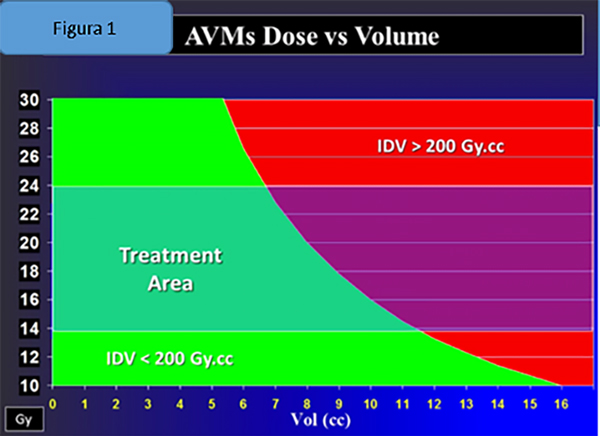

Otro factor decisivo a la hora de considerar la seguridad de la Radiocirugía es conocer la limitante de dosis. En los casos de las MAV´s intrincadas en medio del parénquima cerebral, la misma se define utilizando un parámetro denominado Integral de Dosis: que relaciona volumen con dosis. (Figuras 1 y 2)

Figura 1: Gráfico Dosis-Volumen donde se observa el área por el cual nos debemos manejar a la hora de prescribir dosis para obtener buenos resultados y de forma segura.